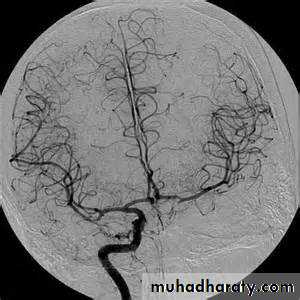

• Conventional catheter angiography definitively assesses large, medium-sized, and sizable small vessels for AVMs, vasculitis, and other arteriopathies

Consider catheter angiography for

• young patients

• patients with lobar hemorrhage

• patients without a history of hypertension

• patients without a clear cause of hemorrhage who are surgical candidates.

Vessels imaging

10-20% of patients with clinically diagnosed SAH (on CT and/or lumbar puncture) have negative angiographic findings. A repeat angiogram is usually required in 10-21 days in such cases.MD-CTA derives from its noninvasiveness and a sensitivity and specificity comparable to that of cerebral angiography. This technique is beneficial in very unstable patients who cannot undergo angiography or in emergent settings prior to operative intervention for clot evacuation